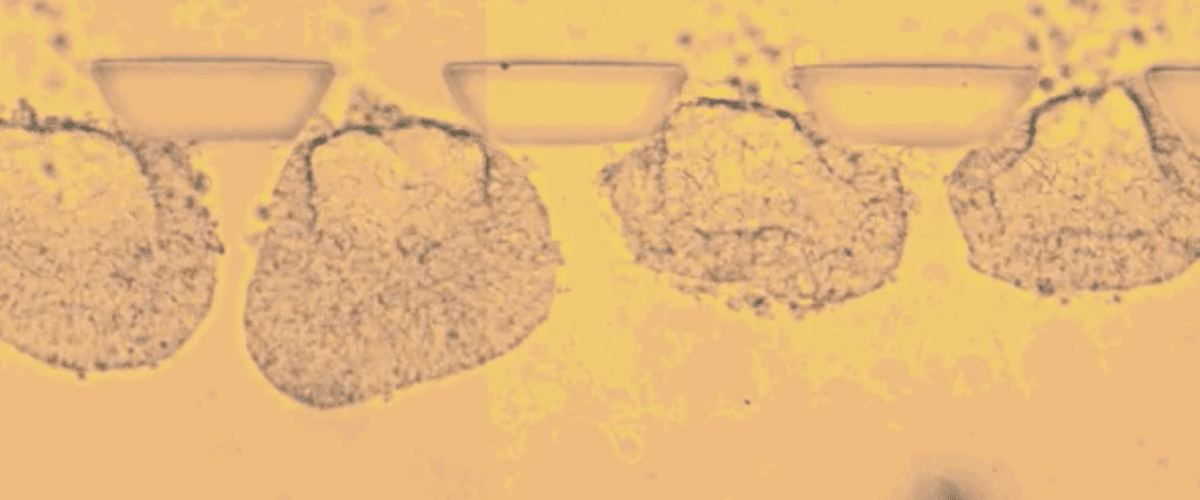

Исследователи из Мичиганского университета разработали модель, имитирующую эмбрион на первых стадиях развития. Для этого они поместили стволовые клетки на микрожидкостный чип, который по мере развития зародыша точечно подавал химические сигналы, стимулирующие формирование тех или иных тканей.

Как сообщает Technology Review, технология была разработана еще несколько лет назад. Сейчас же команда научилась доводить до состояния эмбриона 90% клеток.